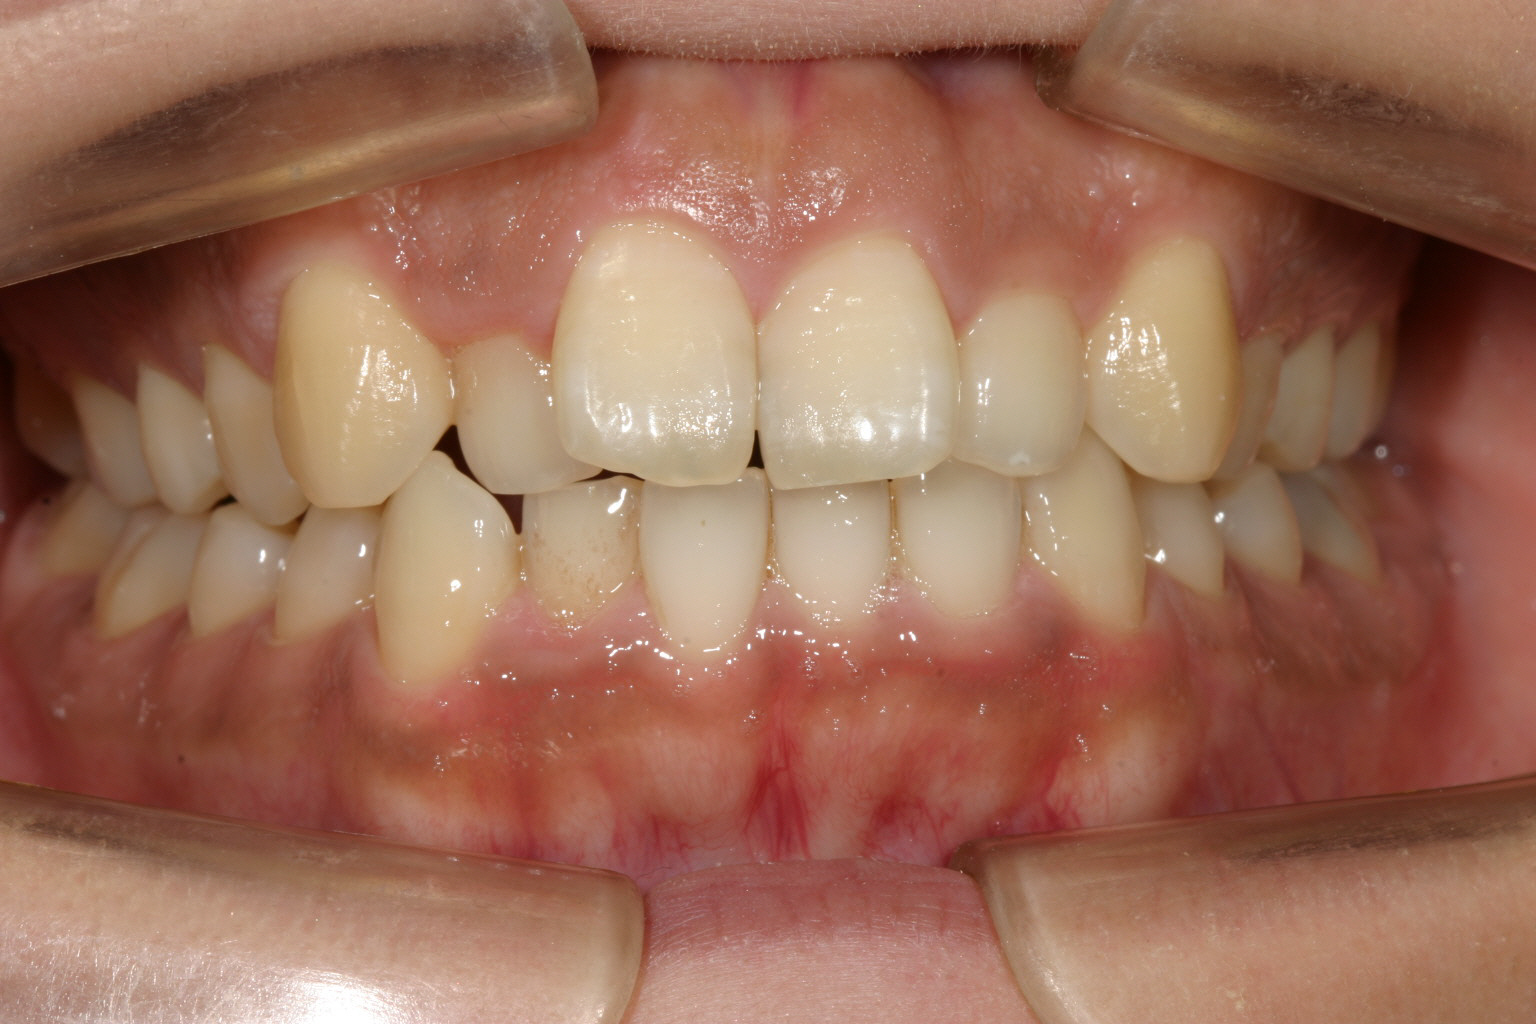

前歯が飛び出して少し翼状捻転しています。

下顎は少しの叢生です。

少しオーバージェットが大きいですね~